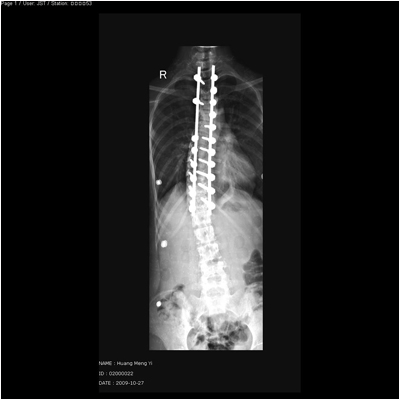

脊柱侧弯和后凸畸形病例一:女性,15岁,诊断:脊柱侧弯

术后正位平片